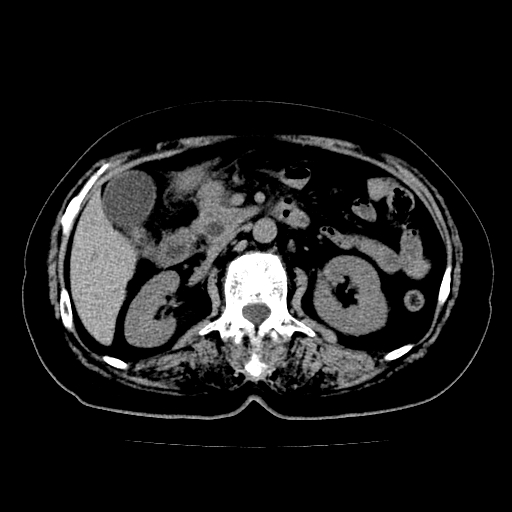

以下是引用lujiandong在2009-2-8 9:37:00的发言:[br]从所发的ct平扫图象上看,胆总管明显增粗,从上向下逐渐变细,是否有泥沙样结石,建议薄层重建;胰腺形态基本正常,左侧肾前筋膜轻度增厚。可以考虑:轻度单纯性胰腺炎,建议ct增强扫描。